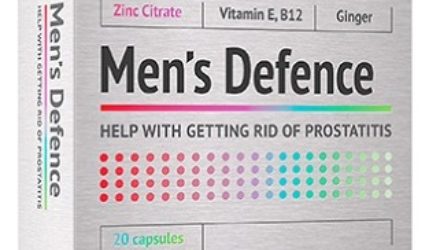

Men’s Defence — 18 отзывов о Менс Дифенс (развод или правда): реальные и отрицательные мнения покупателей и специалистов, где купить, цена, инструкция по применению

Профессиональное средство от простатита Men’s Defence отзывы получает от покупателей только положительные. Более того, препарат хвалят и сами специалисты, отмечая его...